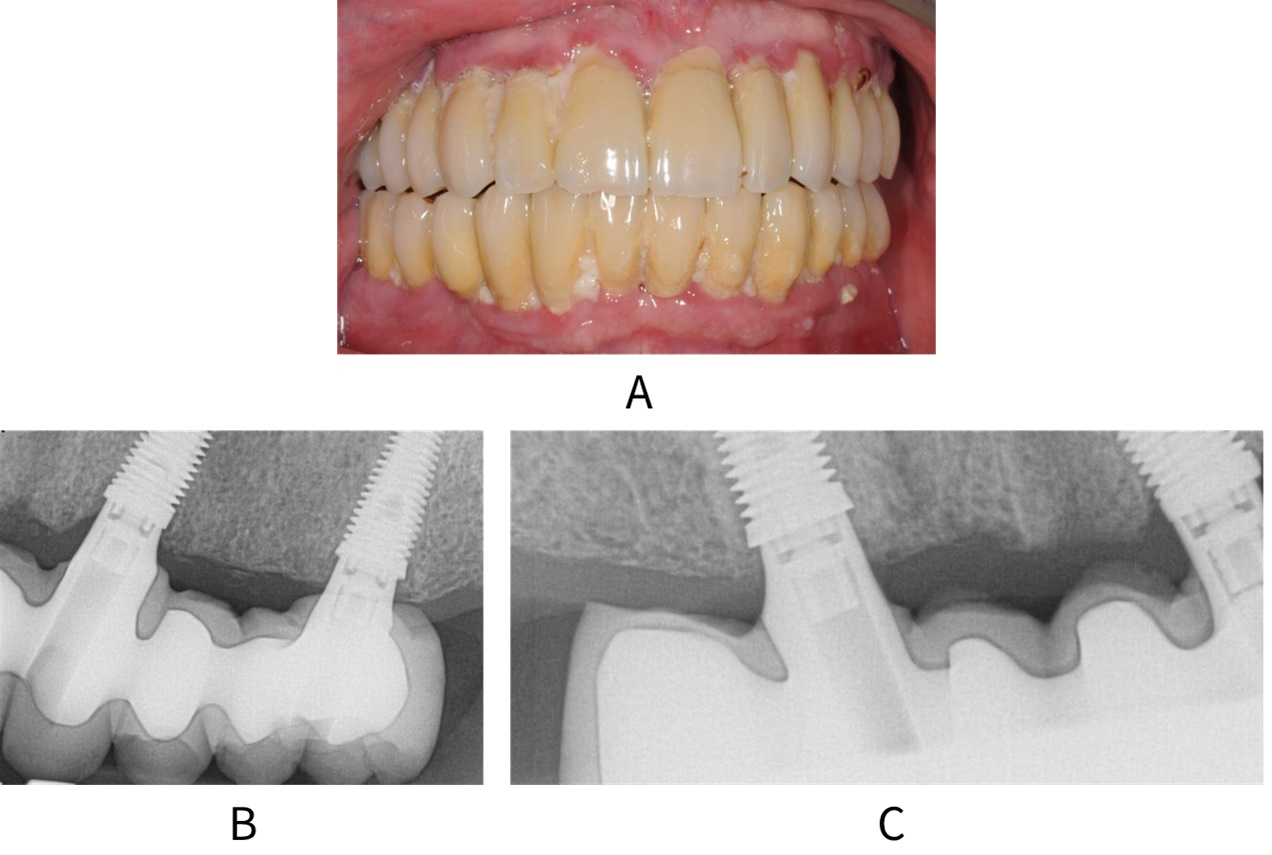

Peri-implant mucositis is mucosal inflammation in the absence of marginal peri-implant bone loss beyond crestal bone level changes resulting from initial bone remodelling.10, 123 Clinical signs include redness, swelling, bleeding on gentle probing at more than one site around the implant, and suppuration (see figure: Peri-implant mucositis).

A: Patient with full upper and lower arch restorations and peri-implant mucositis. Radiographs B and C show no bone loss around the implants